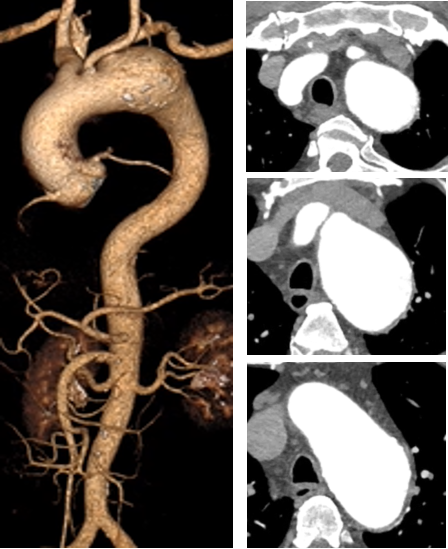

★ 病例10

王某,男,67岁,“查体发现主动脉弓部动脉瘤7天”入院,主动脉CTA提示:主动脉弓部夹层动脉瘤。

术前CTA

术前造影

术后造影

手术用时 80 分钟